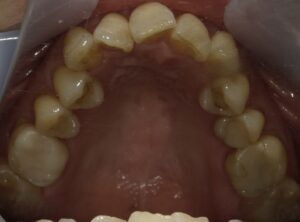

【症例2】50代・矯正は難しいと言われ半ば諦めていたガタガタの改善

「数カ所の歯科医院で相談をしたが、矯正が難しいと言われ諦めかけていた」という50代女性のケースです。前歯が元々欠損しているため真ん中を合わせることはできませんが、ガタガタはIPRや側方拡大を行い治すことができました。

仕上げに前歯のすり減りをダイレクトボンディングで直し、より整った印象にしています。

- 治療方法: ワイヤー矯正上下

- 治療期間: 12ヶ月

- 治療費用: 77万円(税込)

- 治療のリスク・デメリット:ブラックトライアングル

- ポイント: 比較的短期間のプランで、前歯の見た目と清掃性を大幅に向上させました。